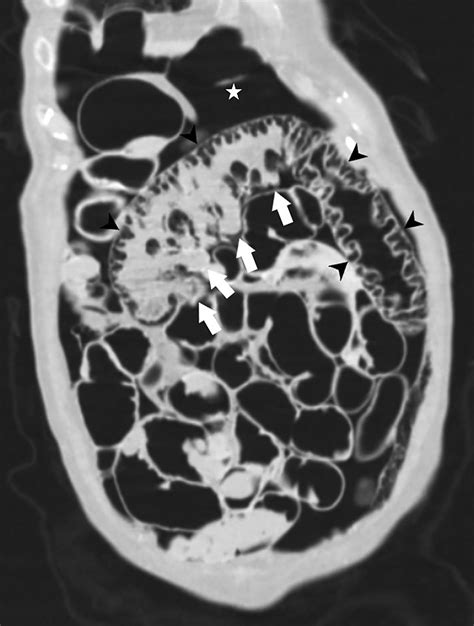

CT Scan The gold standard; provides detailed visualization of gas cysts.

When reviewing imaging, radiologists look for the specific appearance of "bubbly" gas collections along the serosal or submucosal surfaces. Differentiating these cysts from free air (pneumoperitoneum) is the most critical step for the radiologist to ensure the patient is not facing a surgical emergency.